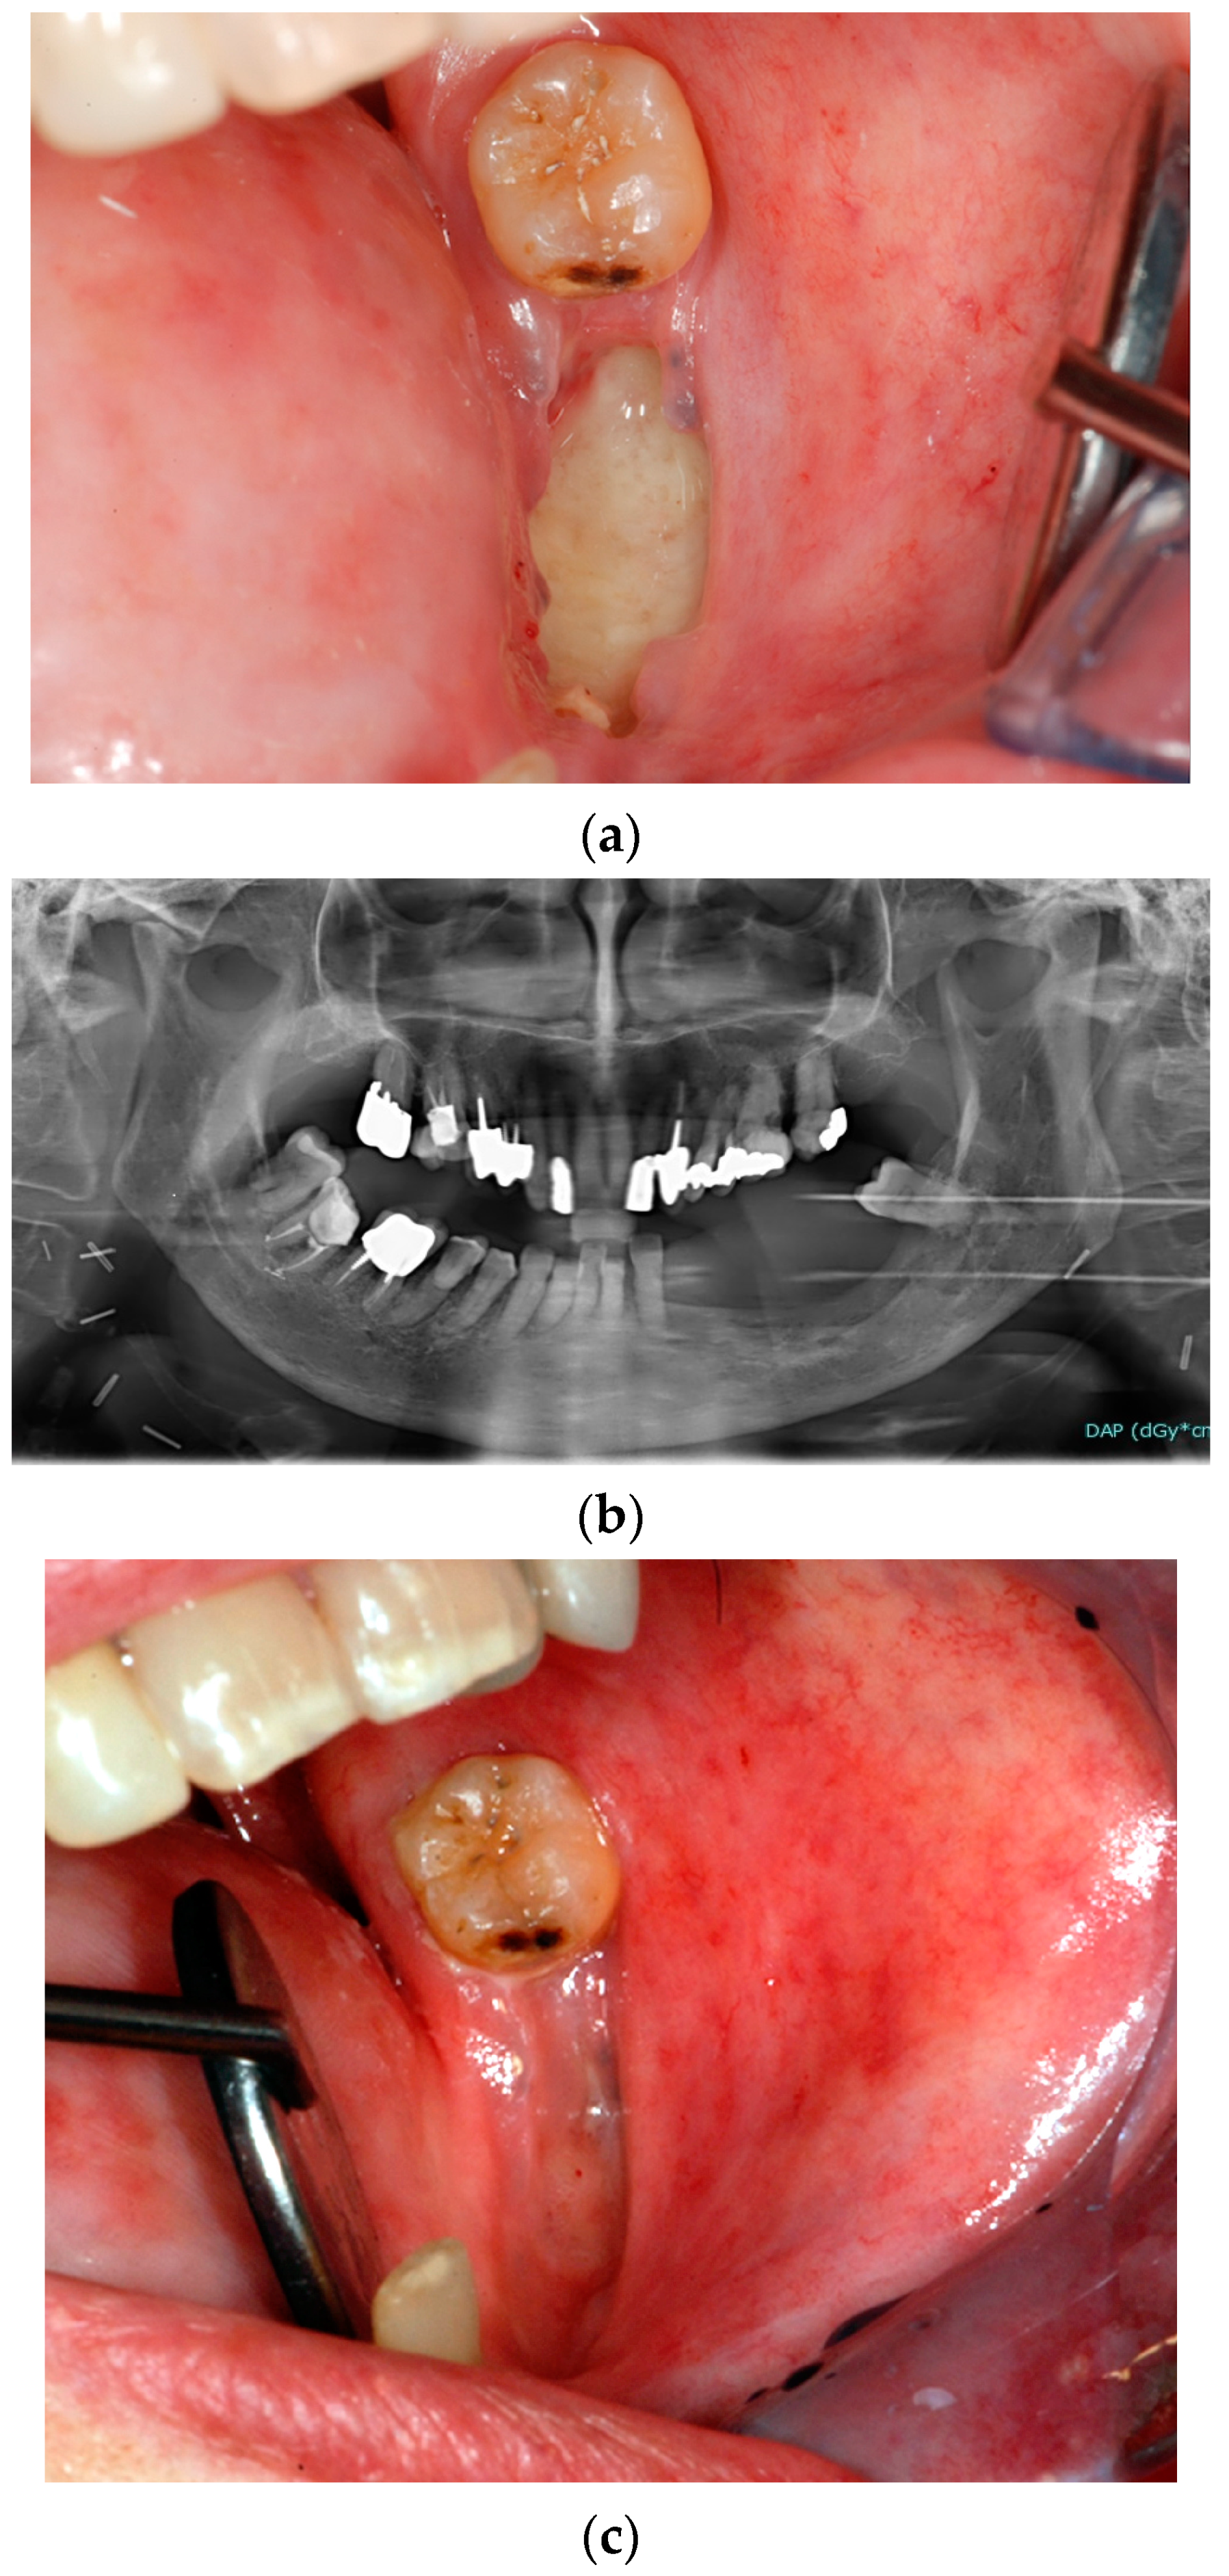

3.1.1. Dental Extractions

3.2. Preventive Strategies for Reducing the Risk of ORN Related to Dental Extractions